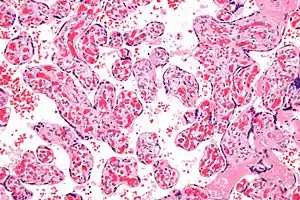

| Micrograph of a chorangiosis. H&E stain. | |

Chorangiosis is a placental pathology characterized by an abundance of blood vessels within the chorionic villi.

Commonly used criteria from Altshuler[2][3] are: "a minimum of 10 villi, each with 10 or more vascular channels, in 10 or more areas of 3 or more random, non-infarcted placental areas when using a ×10 ocular." The Altshuler criteria are not theoretically rigorous, as they do not define the area. Normal villi have up to five vascular channels.[3]